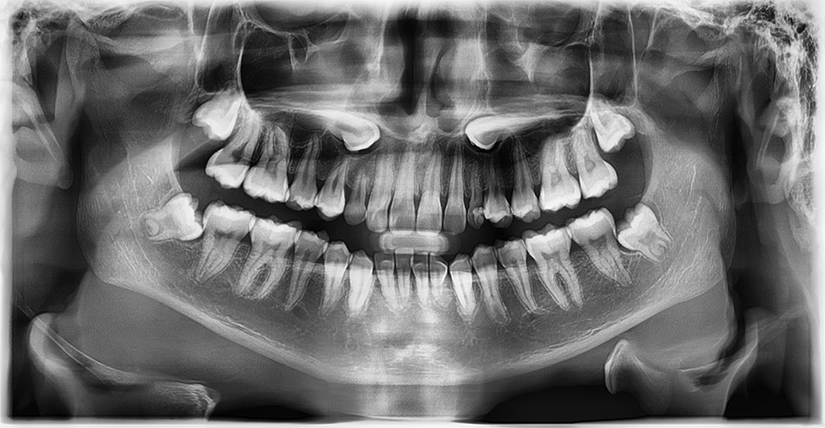

Diagnosticul de certitudine se stabilește în cabinetul medicului ortodont, care va corobora examenul clinic (palparea unei umflături în gingie sau în cerul gurii) cu investigațiile imagistice. Tehnologia modernă, precum CBCT-ul (tomografia computerizată cu fascicul conic), este standardul de aur pentru a vedea exact poziția tridimensională a dintelui.

- Radiografie panoramică: Oferă o imagine de ansamblu a tuturor dinților și maxilarelor.

- CBCT (3D): Este crucial pentru a vedea raportul caninului cu rădăcinile dinților vecini și pentru a planifica direcția de tracțiune fără a afecta structurile din jur.